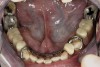

Figure 4  Intraoral occlusal view of maxillary dentition presenting excessive signs of wear.

Figure 4

Initial examination revealed a partial edentulous patient with extensive wear of the maxillary anterior teeth and moderate wear in the mandibular teeth (Figure 1, Figure 2, Figure 3 , Figure 4, Figure 5, Figure 6 and Figure 7). The patient's maxillary and mandibular RPDs also showed excessive wear and multiple signs of fractures (Figure 2 and Figure 3). The patient had been wearing a mandibular nightguard for 8 years.

A history of bruxing and consumption of acidic and carbonated drinks were reported. The clinical examination revealed severe tooth wear extending to the cervical level of the palatal surfaces of the maxillary teeth in some areas. Therefore, TSL was diagnosed as being caused by a combination of attrition and erosion.